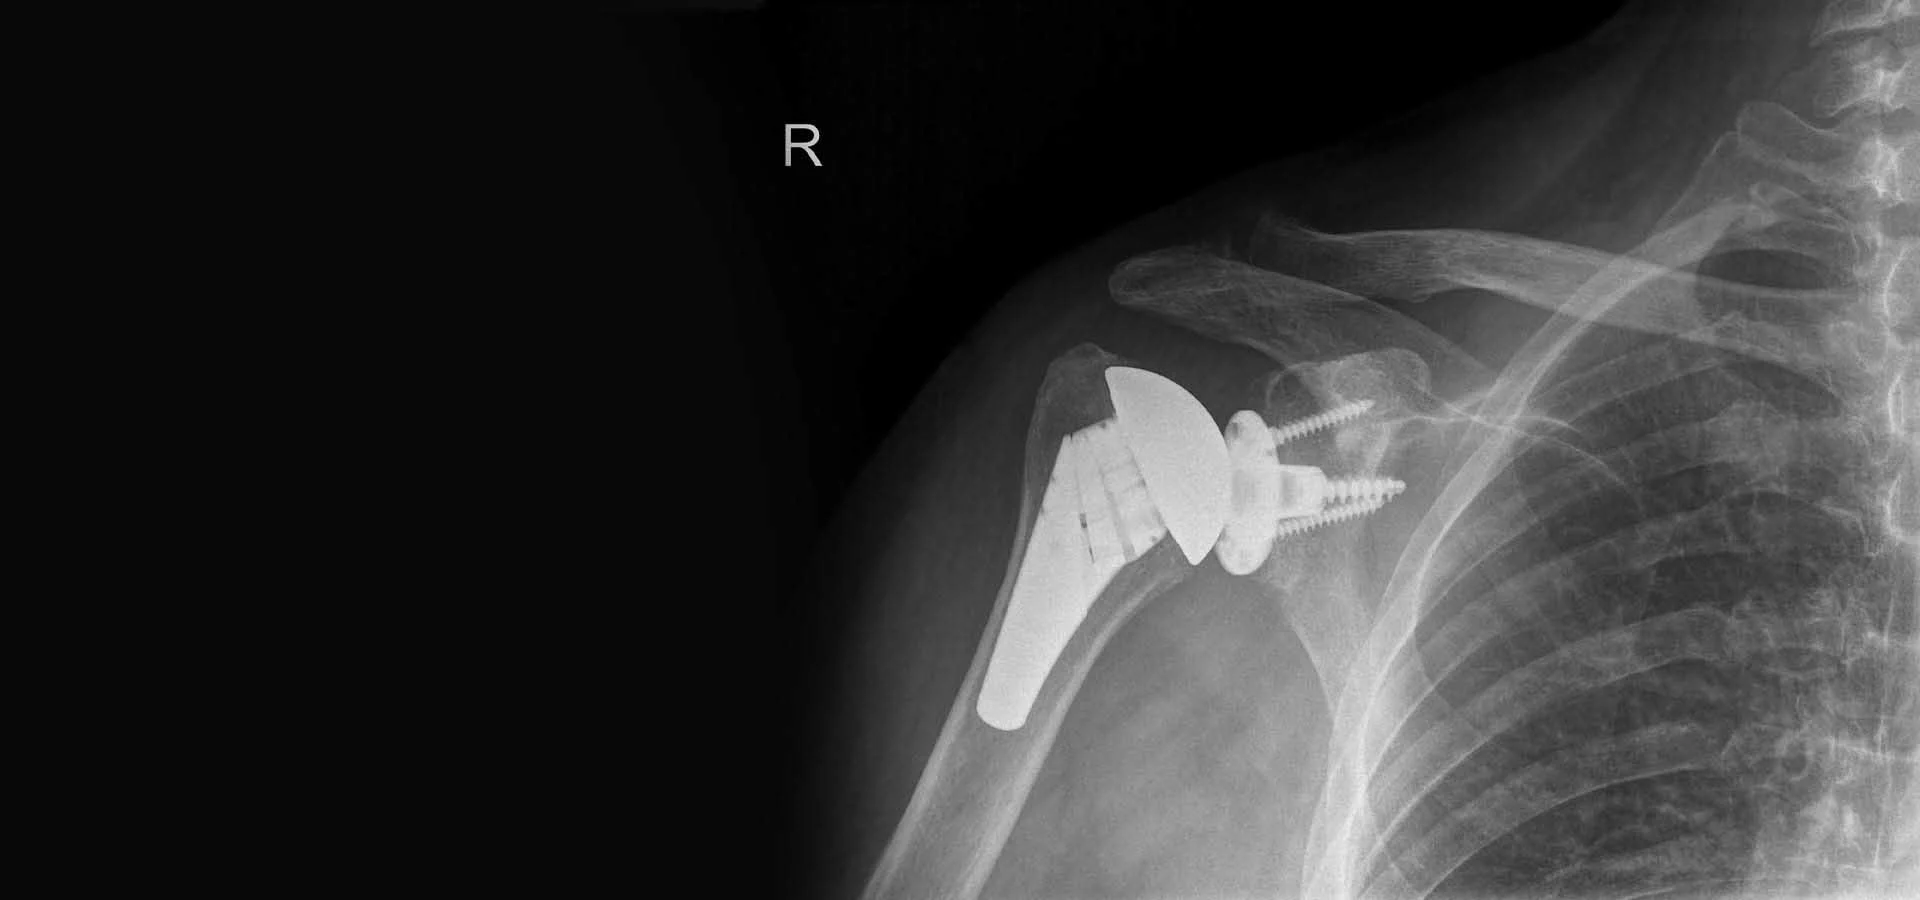

Ο ορθοπεδικός σας θα σας καθοδηγήσει σχετικά με τις απαραίτητες εξετάσεις και διαγνωστικά τεστ που θα πρέπει να υποβληθείτε πριν από την επέμβαση. Αυτό περιλαμβάνει ειδικές λήψεις ακτινογραφιών, μαγνητική τομογραφία (MRI) καθώς και αξονική τομογραφία τρισδιάστατη ( 3CD CT) για ένα ακριβή προ εγχειρητικό σχεδιασμό ως προς το κατάλληλο είδος, τα χαρακτηριστικά και το μέγεθος της νέας πρόθεσης ώστε να εφαρμόσουμε αυτό που ονομάζουμε εξατομικευμένη αρθροπλαστική ώμου .